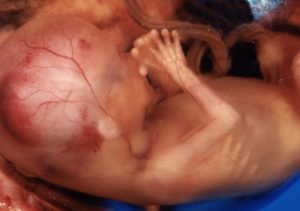

Плод на 17 неделе беременности начинает обрастать жирком. Под кожей формируется прообраз будущего жирового слоя, который будет участвовать в теплообменных процессах. Сама кожа покрывается первородной смазкой – веществом бело-кремового цвета, которое выполняет защитную функцию. Повышается чувствительность кожного покрова детки, в частности в области живота и ягодиц.

Копчико-теменной размер плода на 17 неделе беременности достигает в среднем 13 см, а вес может доходить до 140 г. Кроха уже такой большой, как раскрытая ладонь взрослого человека. Он очень быстро растет и развивается и на 17 неделе беременности уже слышит доносящиеся извне звуки, узнает голоса, ощущает ваши эмоции и настроение.

- Еще один важный момент развития – малыш на 17 неделе беременности приобретает жировой слой. Пока он малозаметный и кожа плода имеет ярко красный оттенок. Но ближе к моменту родов, жировая клетчатка будет активно расти, ведь она выполняет важные функции – защищает организм от перепадов температур и принимает участие в процессах теплообмена.

Совет! На этом этапе процентное содержание жира в теле плода составляет всего около 0,5%. К моменту родов его количество увеличится до 60-70%. Благодаря наличию подкожной жировой клетчатки кожа малыша выглядит не ярко-красной, а бело-розовой. Чем с большим весом родится ребенок, тем более светлая у него кожа.

Размер плода на 17 неделе беременности составляет около 11-14 см в длину, а его вес – чуть более 100 граммов. Таким образом, на 17 неделе беременности размер плода можно сравнить с крупной грушей.